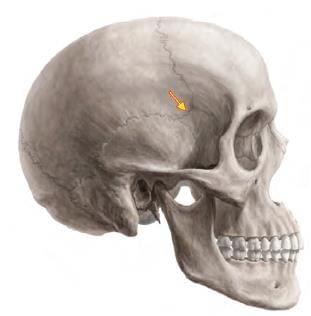

A fracture at the marked arrow (pterion) leads to bleeding of which artery? (AIIMS June 2020)

Detailed Solution for Test: Anatomy - 3 - Question 12

The highlighted area is the pterion, beneath which lies the anterior division of the middle meningeal artery, which may bleed if a fracture occurs at this location. The pterion marks the junction of four bones: the frontal, parietal, and temporal bones, along with the greater wing of the sphenoid bone. The central point of the pterion is referred to as the Sylvian point, where the cranium is notably thin.

• Its immediate deep relationships include the frontal (anterior) branch of the middle meningeal artery, its accompanying vein, and the stem of the lateral (Sylvian) sulcus of the cerebrum.

• The lateral sulcus extends posteroinferiorly from the Sylvian point, situated near the region of the pterion.

A fracture in this area can damage the middle meningeal artery, potentially leading to extradural haemorrhage. The pterion is crucial for the precise placement of burr holes for evacuating extradural haematomas. In neurosurgery, the pterional craniotomy is a frequently used technique to access the middle cranial fossa. Additionally, the pterion is the location of the anterolateral fontanelle, which closes at around six months after birth.